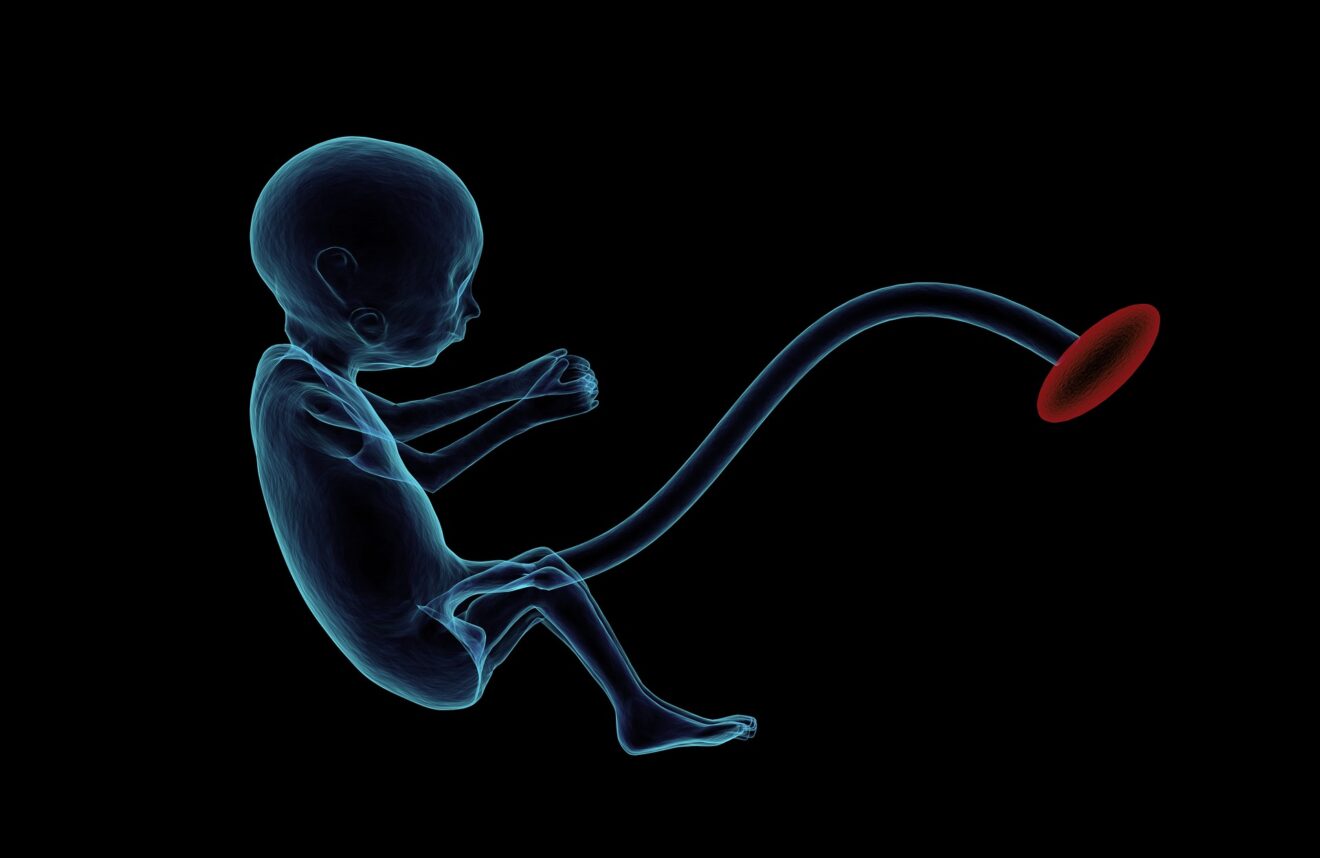

Per valutare lo stato di salute del feto, è molto utile verificare la struttura cardiaca del nascituro. A questo scopo, vengono effettuati dei test come l’ecocardiografia fetale. Questo test permette di tenere sotto esame il cuore del feto, tracciando la sua anatomia.

L’ecocardiografia fetale è un esame non invasivo e per nulla rischioso. Tramite gli ultrasuoni, i segnali vengono trasmessi da una sonda all’ecografo, che elabora le onde sonore e mostra poi l’immagine al monitor. Questo test permette di esaminare la parte alta del cuore. Così possono essere scoperte eventuali patologie cardiache congenite e malformazioni. Permette perciò di intervenire preventivamente, nel caso in cui il medico lo ritenga necessario. L’ecocardiografia non è infatti uno di quegli esami che i medici fanno normalmente alle gestanti.

L’ecocardiografia permette inoltre di rilevare il funzionamento cardiaco del feto, esaminando i flussi del sangue. Per tale scopo si ricorre all’aiuto del Doppler che, in base alla qualità del suono, permette di analizzare la qualità del flusso sanguigno. Se non si verificano delle condizioni poco ottimali, come quella del feto mal posizionato, l’esame dura all’incirca una ventina di minuti. Per svolgere correttamente l’esame, infatti, gli ultrasuoni vengono indirizzati perpendicolarmente rispetto al petto del feto.